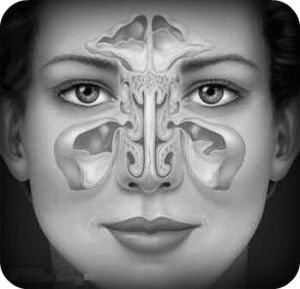

Опис патологічного процесу

Кіста пазухи носа вважається досить поширеним захворюванням. Найчастіше вона діагностується випадковим чином. Наприклад: рентгенологічне обстеження з метою діагностики іншого захворювання.

У процесі формування кісти утворюється міхур, що містить запальну рідину. Він перешкоджає відтоку секреторною рідини в залозах, яку містить слизова оболонка носа.

причини захворювання

Слизова оболонка носа встелена безліччю спеціальних залоз, функція яких

полягає у виробленні слизу. Вона необхідна для зволоження носової порожнини.

Кожна з залоз має проток, який пропускає цю слиз через себе. Саме повна або часткова закупорка цих проток впливає на утворення кісти носової пазухи.

Слиз, що надходить в проток, яка не має можливості потрапити в носову порожнину, накопичується, формуючи кісту.